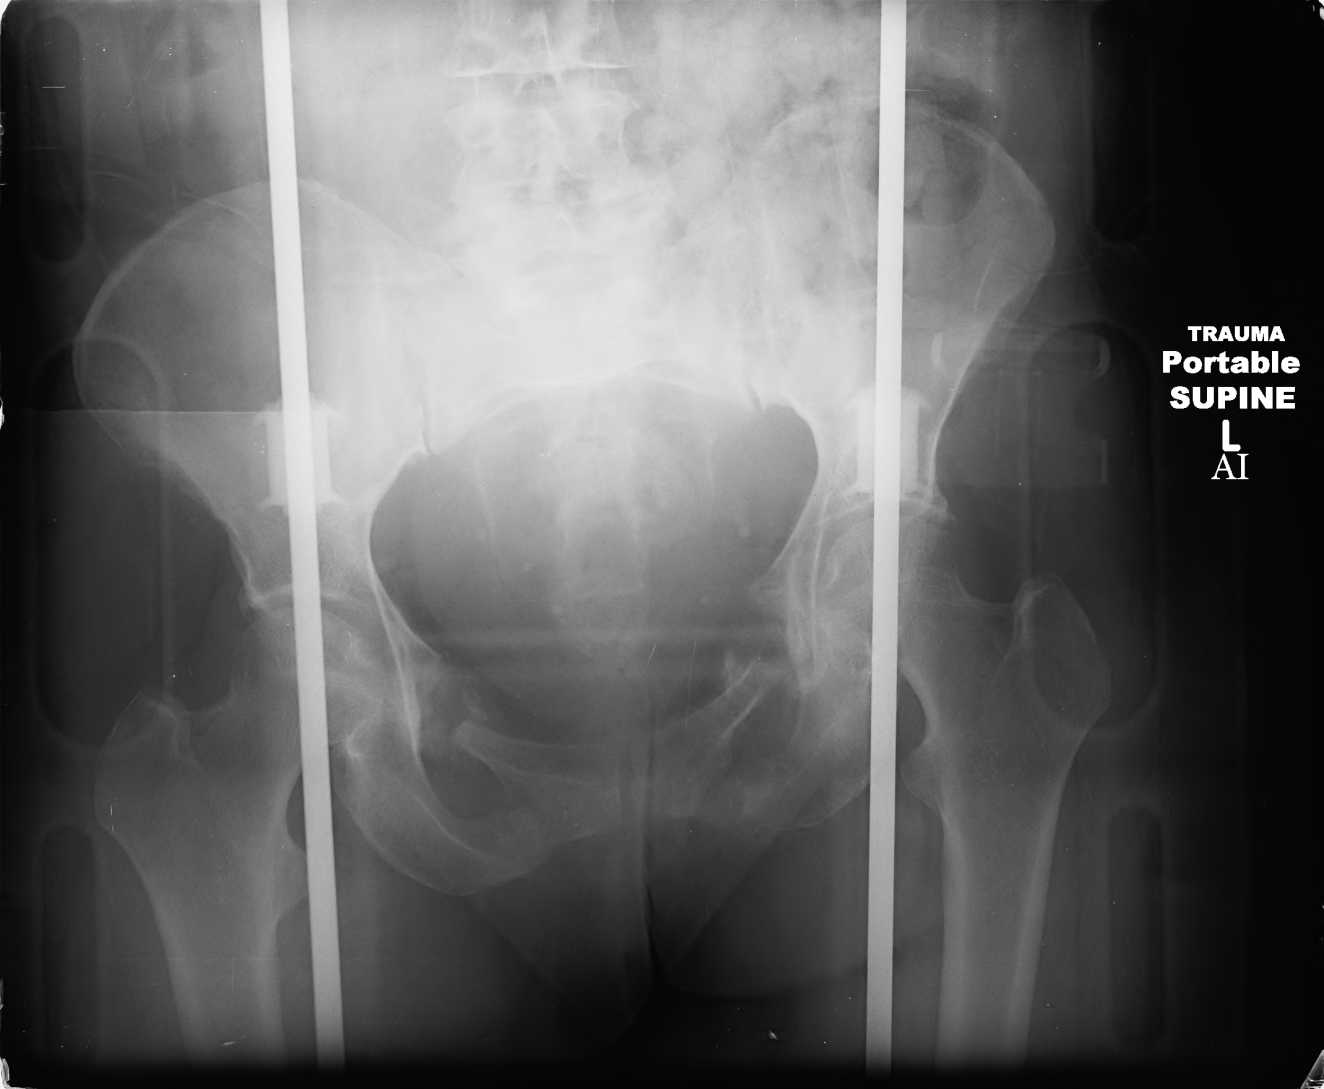

Here are a recent patient’s example slides...

54 yo Female Fell c/o Pain

Initial Films

?Instability on Exam - Limited by Pain

NonOp Initial Mgmt

3 Months After Fall

Continued Pain & Immobility

(+) Instability to Compressive Manual Exam